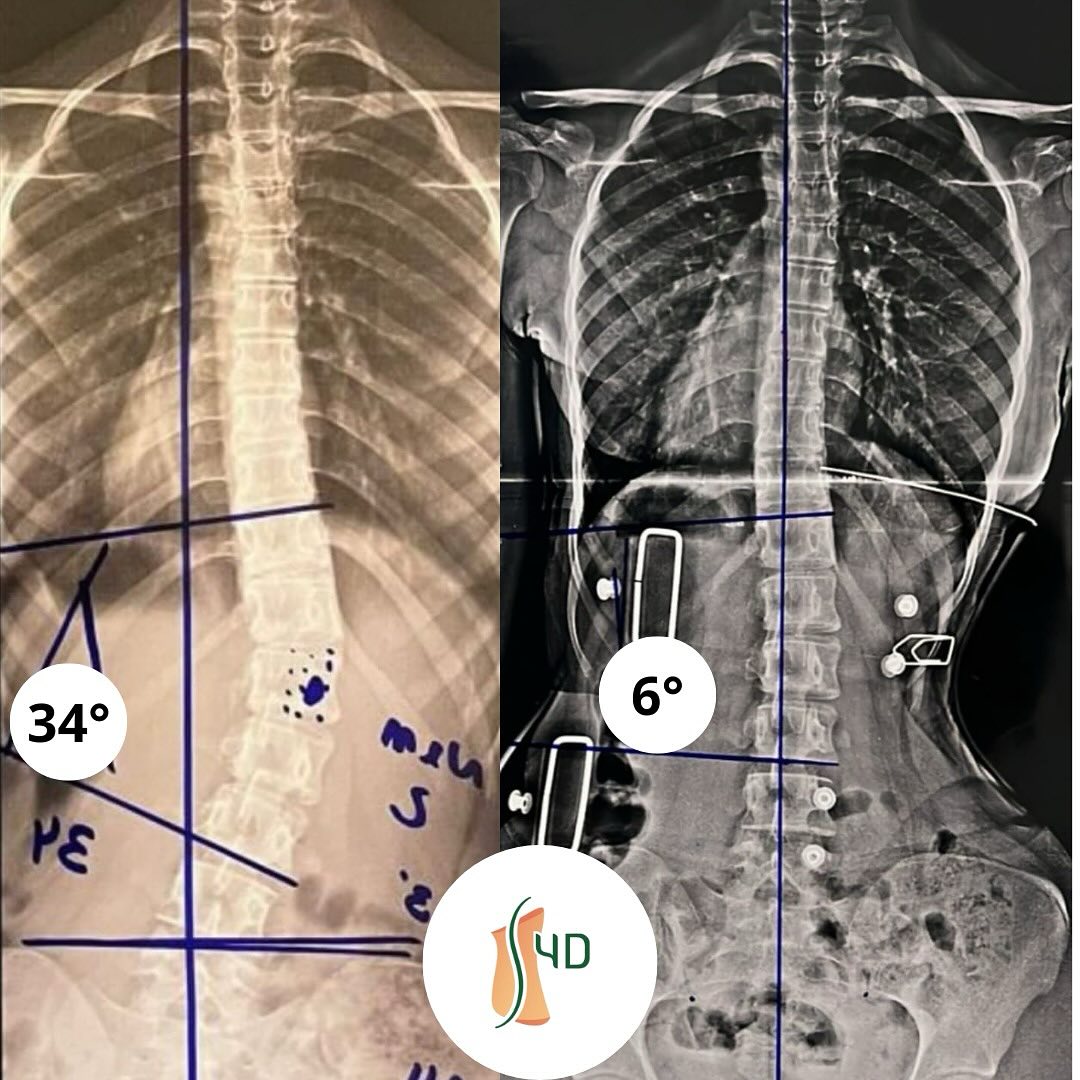

Redução de 34° para 6°

Resultados excepcionais sem cirurgia